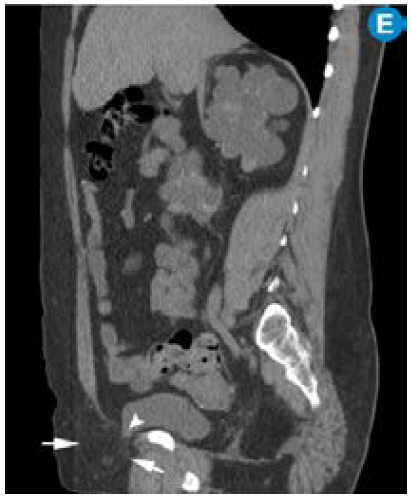

Enfermedad renal poliquística dominante en paciente trasplantado. A) Ecografía renal: múltiples imágenes quísticas que comprometen el parénquima renal bilateral. Continúa.

Figura 1: Enfermedad renal poliquística dominante en paciente trasplantado. A) Ecografía renal: múltiples imágenes quísticas que comprometen el parénquima renal bilateral. Continúa.

B) CT simple corte coronal: riñones aumentados de tamaño con múltiples quistes. C) Ecografía doppler color: riñón trasplantado sin alteraciones. D) CT simple corte sagital: riñón trasplantado (asterisco), riñón derecho con múltiples quistes (cabeza de flecha) y quiste hepático (flecha). Continúa.

Figura 1: B) CT simple corte coronal: riñones aumentados de tamaño con múltiples quistes. C) Ecografía doppler color: riñón trasplantado sin alteraciones. D) CT simple corte sagital: riñón trasplantado (asterisco), riñón derecho con múltiples quistes (cabeza de flecha) y quiste hepático (flecha). Continúa.

E) CT simple corte sagital: hernia inguinal directa derecha (entre flechas) con pequeña porción de la vejiga dentro del saco herniario (cabeza de flecha).

Figura 1: E) CT simple corte sagital: hernia inguinal directa derecha (entre flechas) con pequeña porción de la vejiga dentro del saco herniario (cabeza de flecha).

Fuente: Archivo personal JM.

Por su alta sensibilidad, disponibilidad y bajo costo, la ecografía renal es el estudio inicial con el que se pueden observar riñones grandes con quistes bilaterales, múltiples y tamaño variable (figura 1); sin embargo, es altamente dependiente del operador y es menos sensible para detectar quistes <1cm que se visualizan mejor en la escanografía o en la resonancia magnética 24. Pese a que en la actualidad no existen criterios estandarizados en estas dos técnicas imagenológicas para el diagnóstico de la PKD, la tomografía computarizada (TC) y la resonancia magnética (RM) son más sensibles para el diagnóstico de los quistes en los casos dudosos, la detección de complicaciones, la valoración de la progresión y la respuesta al tratamiento 25 (figura 2).